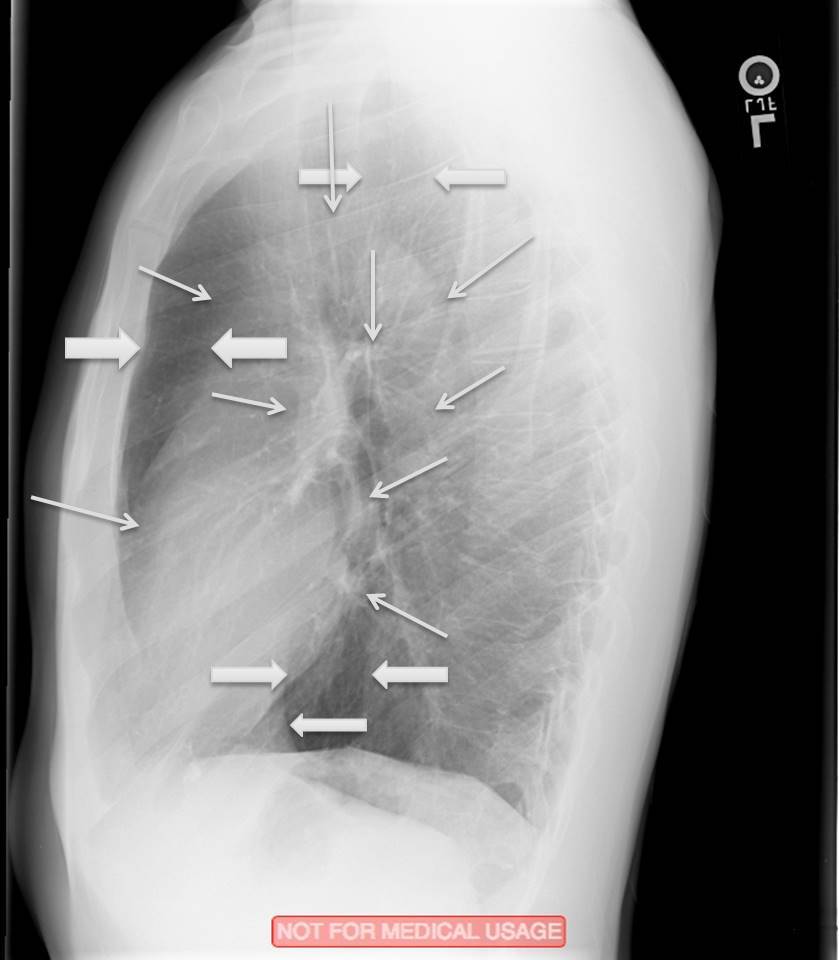

What structures are indicated by the arrows?

Right Paratracheal Stripe

Carina

Left Mainstem Bronchus

Left“3 Moguls”:

Aortic Arch

MPA

Left Ventricle

Right

SVC

Hilum

Right Atrium

Identify the indicated lines/stripes

Junctional Lines

Azygoesophageal Recess

What are the windows of the mediastinum?

Retrosternal

Retrotracheal

Retrocardiac